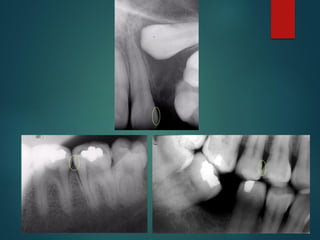

 Incipiente de esmalte

 De esmalte

 Dentinaria superficial

 Dentinaria profunda

 Sobreproyectada en cámara

pulpar

 Penetrante

 Incipiente de esmalte

 De esmalte

 Dentinaria superficial

 Dentinaria profunda

 Sobreproyectada en cámara pulpar

 Penetrante